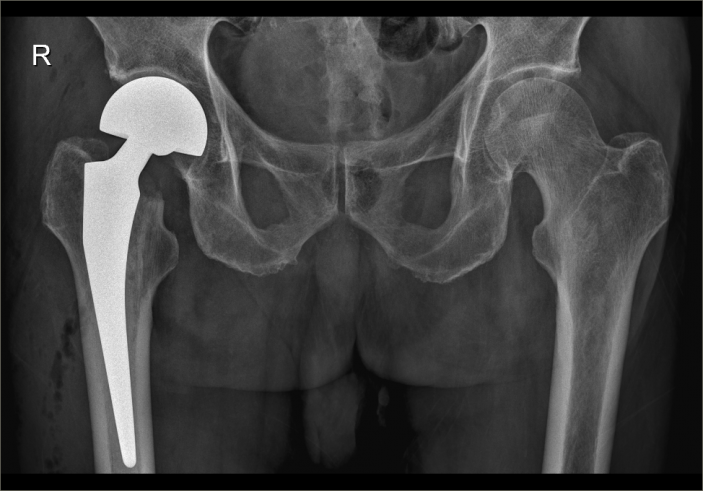

爲了手術能順利開展,骨科主任吳志斌一面邀請我院内科專家會診,對内科疾病進行積極治療,爲手術開展創造有利條件,一面召開術前讨論,精心拟定“右側人工股骨頭置換術”的手術方案,并對術中、術後可能出現的情況制定相應對策。